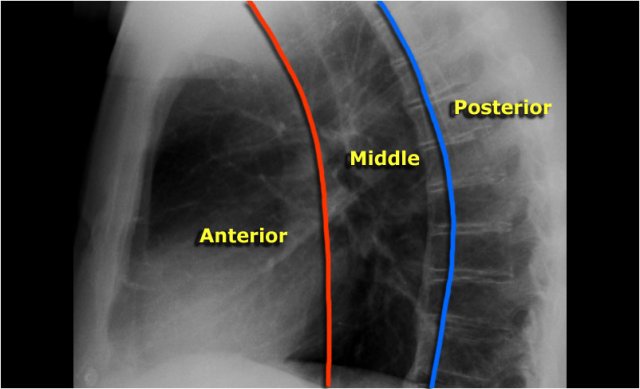

Mediastinum

Mediastinal masses are discussed in more detail in Mediastinal masses.

Here is just a brief overview.

The mediastinum can be divided into an anterior, middle and posterior compartment, each with it's own pathology.